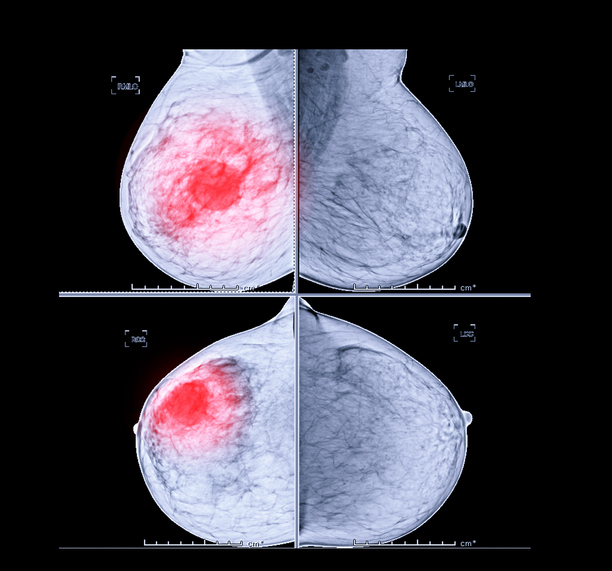

유방암 초기증상 - 덩어리 또는 멍울

유방암을 알아차리는 가장 일반적인 방법은 유방에 덩어리 또는 만져지는 덩어리가 만져지는 것입니다. 멍울은 이전에 본 적 없는 신비한 덩어리이며, 악성이라면 단단하고 고정되어 움직이지 않으며 모양이 불규칙합니다. 모든 멍울이 악성은 아니며 양성일 수도 있으므로 의사와 정기적으로 검진을 받는 것이 중요하므로 이러한 유방암 초기증상을 그냥 지나치지 마시기 바랍니다.